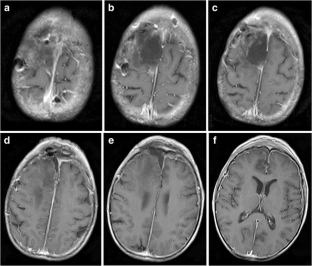

A 68-year-old man in good general health presented with a parasagittal meningioma that recurred following subtotal removal and adjuvant fractionated stereotactic radiosurgery (FSR). The scalp above the tumor location was very diseased and precluded a regular craniotomy for tumor removal. A 4-cm craniotomy was made in the midline forehead, where the skin was normal. A rigid endoscope was advanced under neuronavigation through the interhemispheric fissure, which provided good access with limited retraction, until the tumor was encountered at a depth of 7–8 cm. Two surgeons performed the surgery using a “four-hands technique”. The tumor was removed and the insertion area was resected and coagulated.

The surgery was uneventful, with no coagulation or transection of major veins. A subtotal resection was achieved, and the patient recovered with no neurological deficit.

Fig. 3